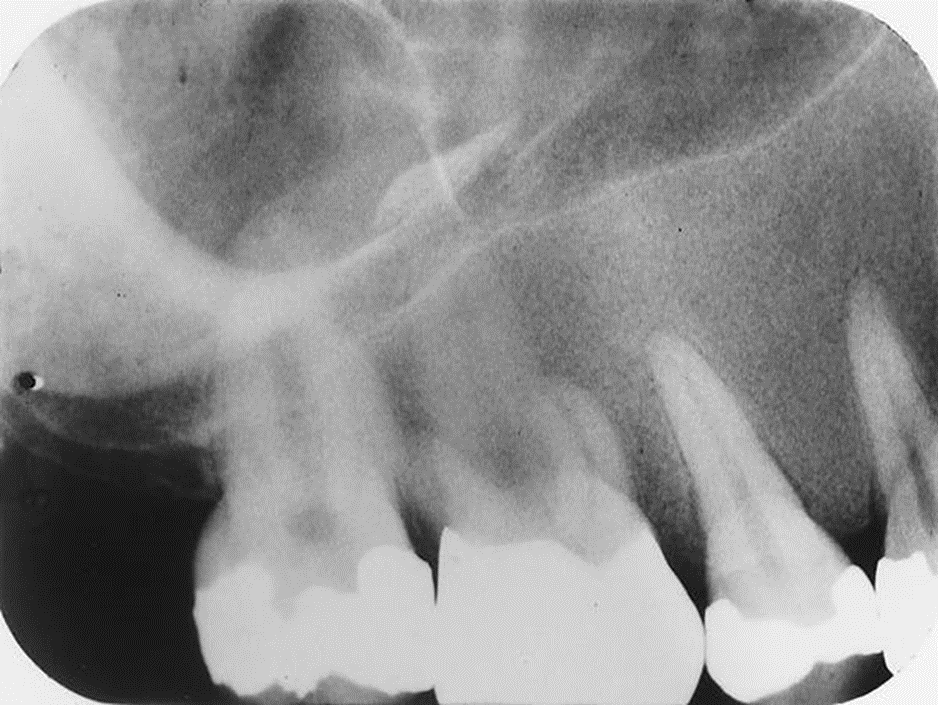

1. Mary is a 67-year-old who was referred to the periodontist. As part of the adiographic examination, this small radiolucent lesion was detected. The teeth were vital. Considering the patient’s age and the location, size, and clinical findings, what is your diagnostic impression?